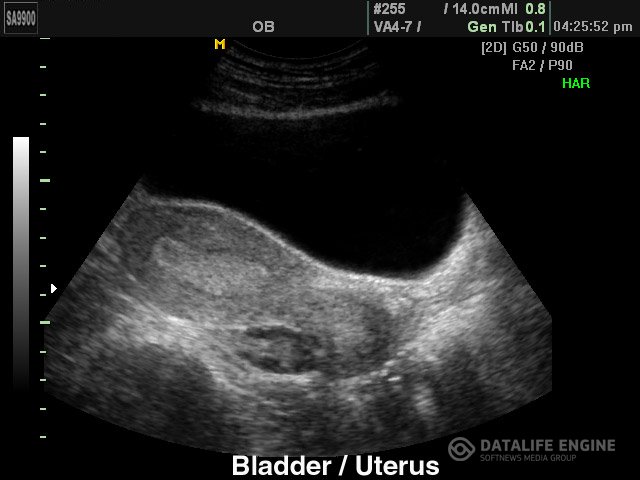

Мочевой пузырь (болезни)Раздражение мочевого пузыря Мочевой пузырь .Народная медицина рекомендует для лечения раздражения мочевого... Мочевой пузырь (болезни)Раздражение мочевого пузыря Мочевой пузырь .Народная медицина рекомендует для лечения раздражения мочевого...